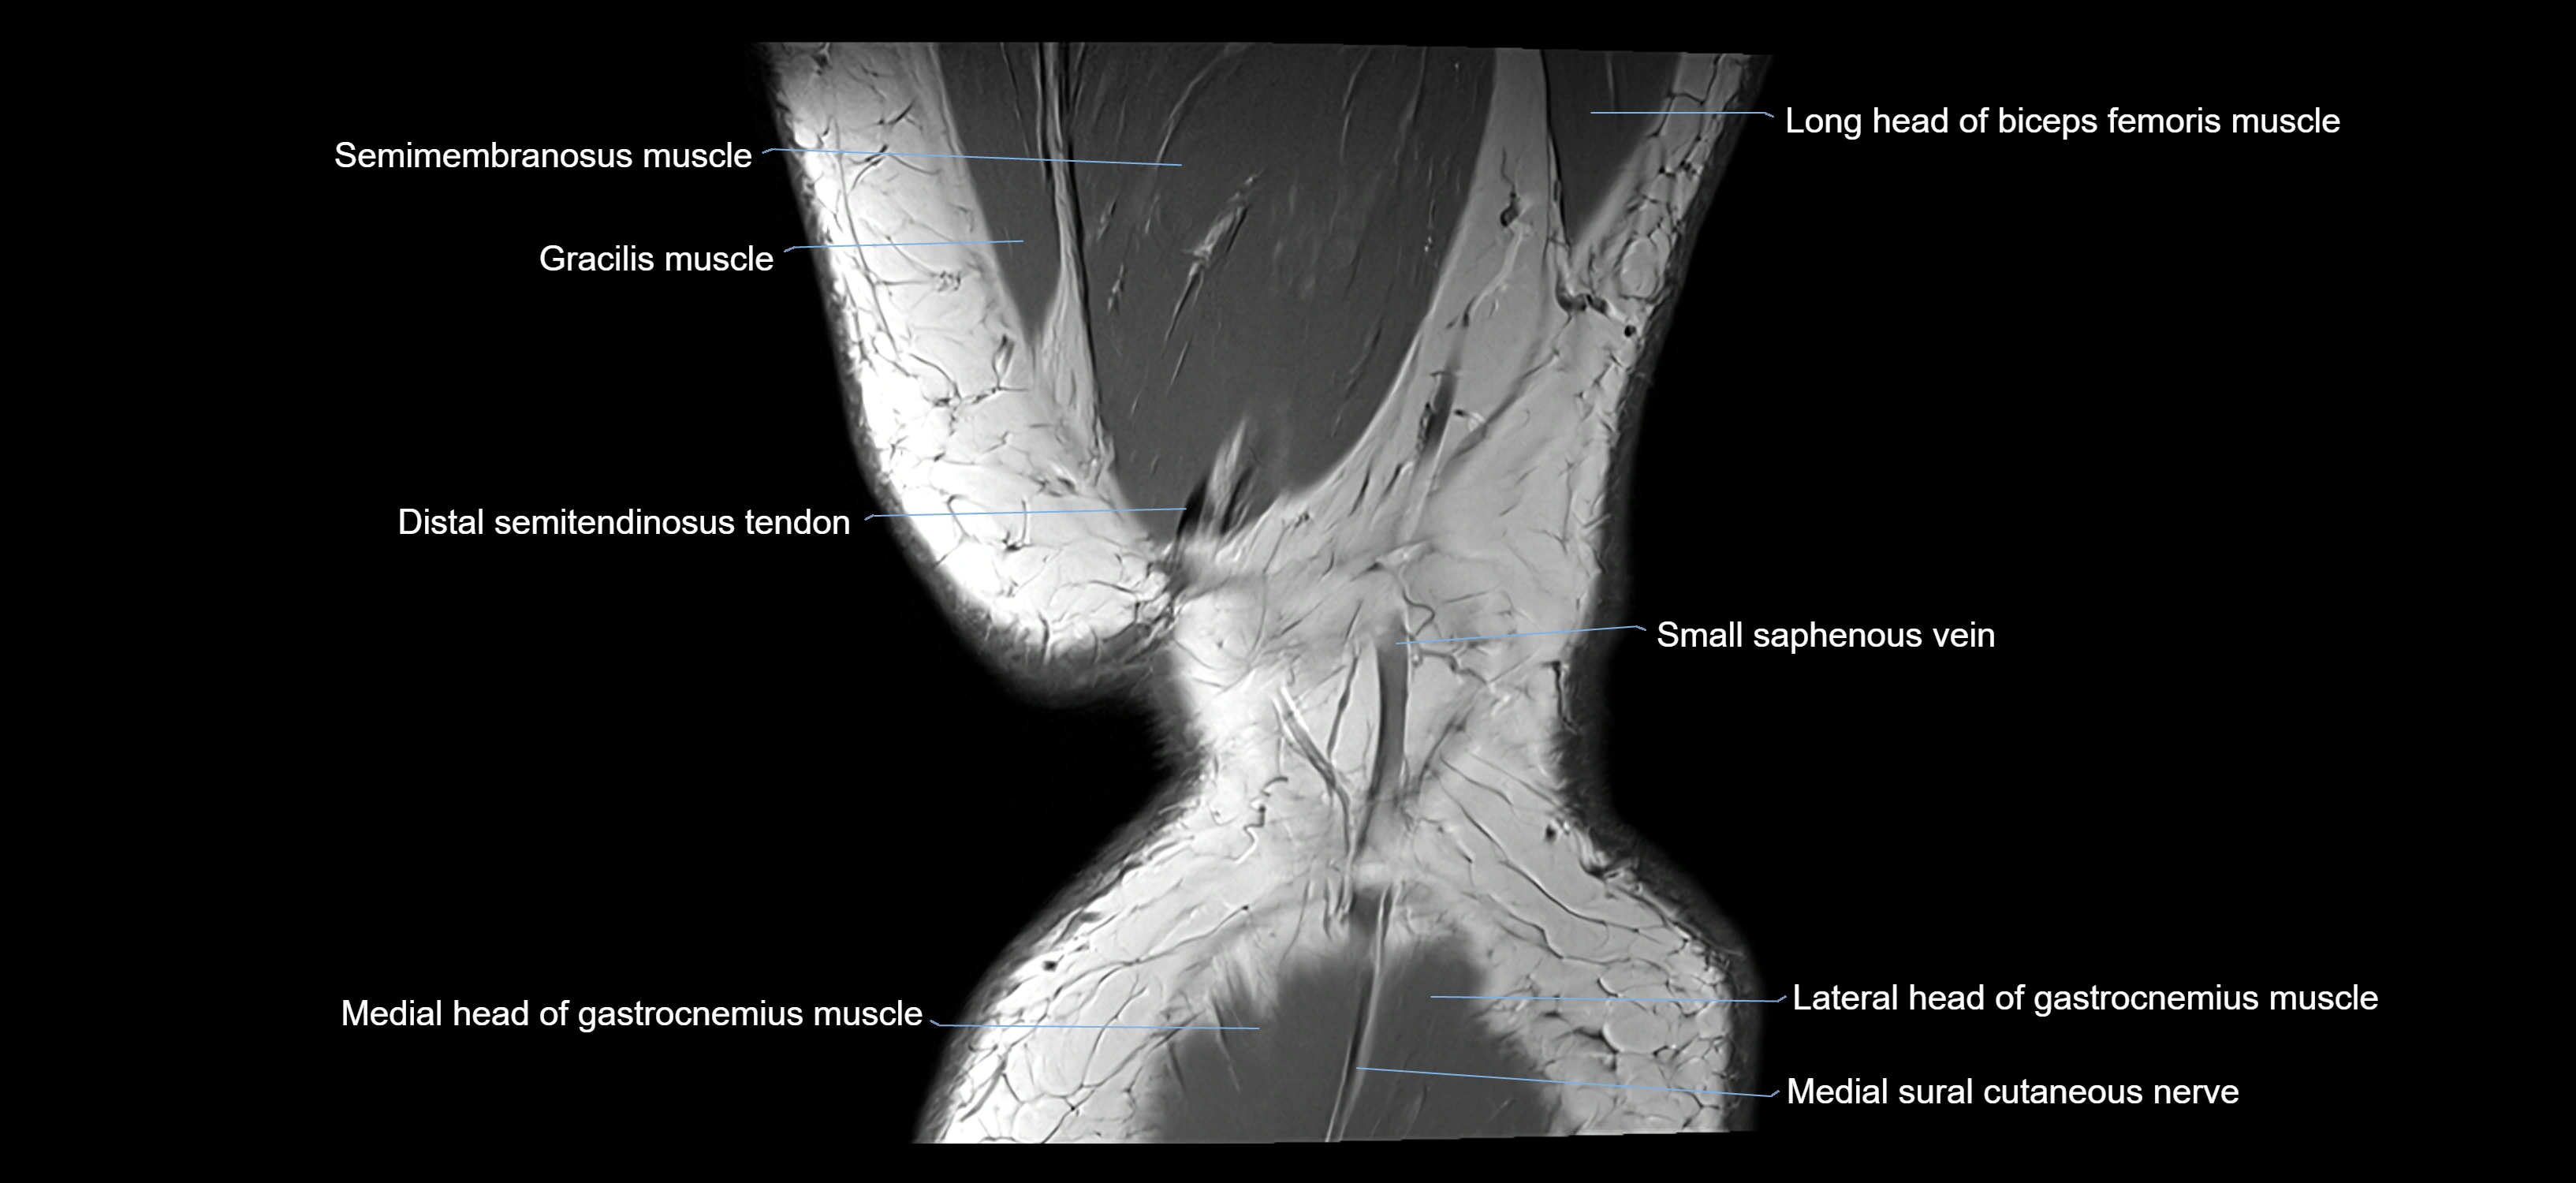

- Biceps femoris muscle (Long head)

- Distal semitendinosus tendon

- Gastrocnemius muscle

- Gracilis Tendon (Proximal)

- Gracilis tendon (Distal)

- Lateral head of gastrocnemius muscle

- Medial head of gastrocnemius muscle

- Medial sural cutaneous nerve

- Semimembranosus muscle

- Semitendinosus muscle

- Small saphenous vein